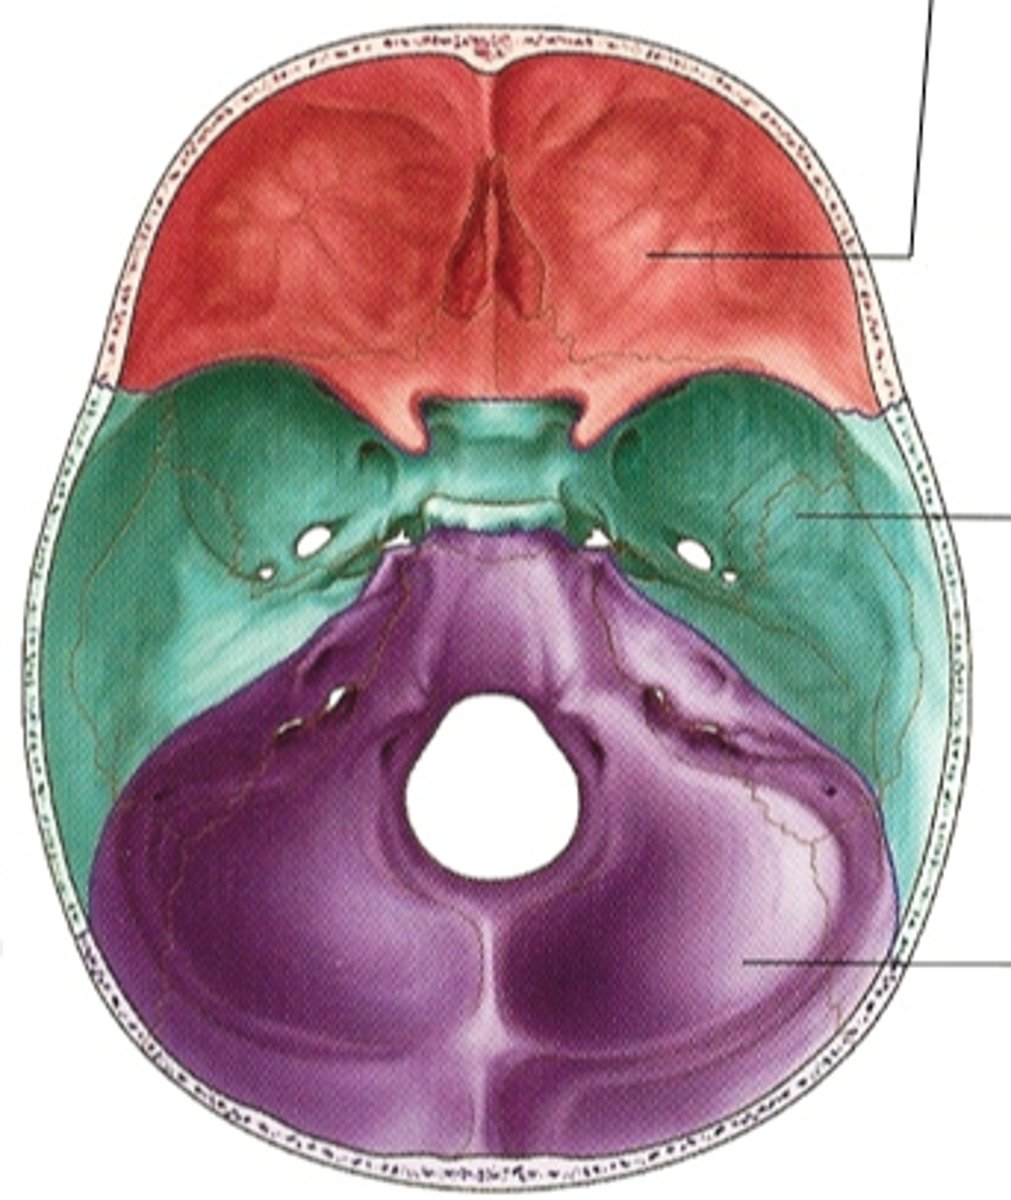

anterior cranial fossa

posterior cranial fossa

middle cranial fossa